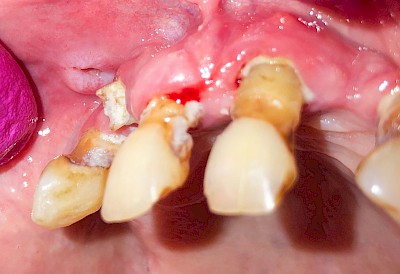

Wundheilungsstörungen

Nach operativen Eingriffen im Bereich der Mundhöhle (Zahn ziehen "Extraktion", Schleimhautprobenentnahmen "Biopsien" oder Tumoroperationen) kann es zu Wundheilungsstörungen mit Schwellungen, Rötungen und Nach-Blutungen, gestörter Sprache oder Kaufunktion kommen. Einzele Gesichtsbereiche können sich warm anfühlen und in seltenen Fällen kann es zu Fieber und reduziertem Allgemeinzustand kommen.

Wundheilungsstörungen24 Bilder